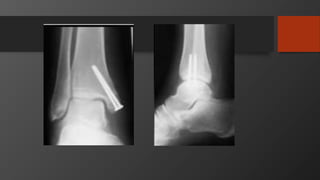

Ankle Fractures

Imaging

• AP, Lateral

• Mortise view

• CT scan

• Especially posterior malleolus

Initial treatment- reduce dislocations

Treatment

• Isolated lateral malleolus fractures

• Isolated medial malleolus fractures

• Bimalleolar fractures

• Posterior malleolus fractures

Syndesmosis injury